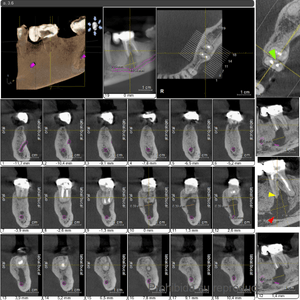

Scanner Cone-Beam CT de última generación

Panorámicas, teleradiografias y CBCT con el sensor más moderno, preciso y de baja dosis.

2Diagnóstico por especialista

Cada caso es único. Informe completo en el menor tiempo posible.

3Entrega digital en 24~48 hrs

Examen e informe directo al clínico para interpretación con exploración clínica.

Diagnóstico certero. Tratamiento efectivo.